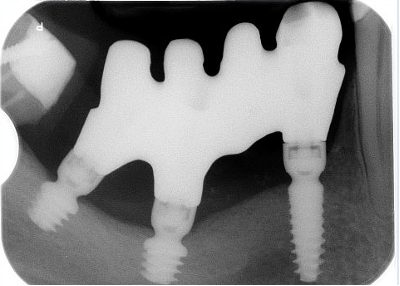

Il paziente, maschio, 63 anni, di etnia caucasica, è stato riabilitato dapprima con impianti tradizionali e impianti zigomatici; successivamente, viene programmato un intervento di implantologia guidata (Figura 5) per gestire la grave atrofia del settore 4 (Figure 6-7).

La metodica con impianti Global D descritta in entrambi i casi ha permesso di disporre di una trousse implantare con frese in grado di realizzare una sottopreparazione o una sovrapreparazione del sito di incorporazione implantare in base alla densità ossea da affrontare nel mascellare e nella mandibola (Figura 8).